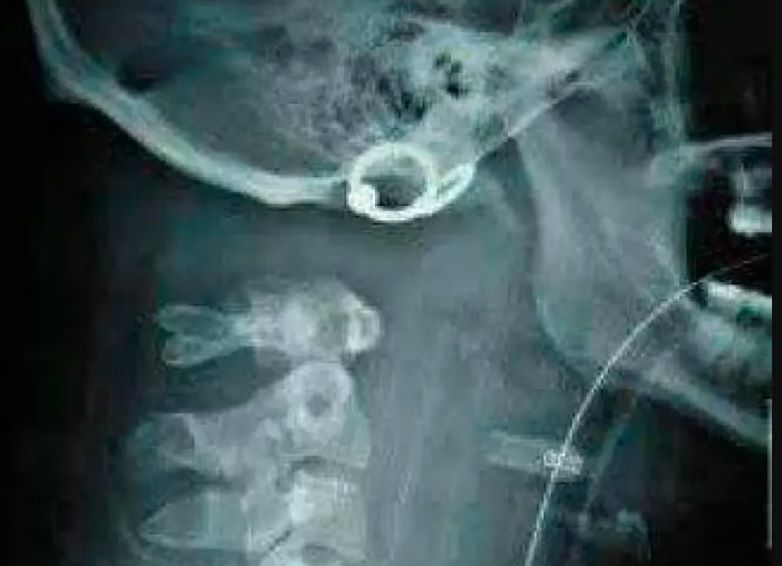

"Oderwanie głowy" występuje więc wewnętrznie, choć w badaniach obrazowych wyraźnie widać przerwę. Takie obrażenie jest śmiertelnie niebezpieczne. Najczęściej doprowadza do zgonu, dlatego każdy, kto przeżyje taki uraz, uważany jest za prawdziwego szczęściarza.

Urwanie głowy